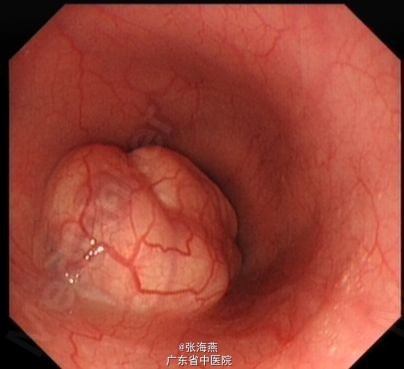

患者,男,22岁 主诉:反复吞咽不适1年余,剑突下隐痛1月余 现病史:患者1年前进食时感吞咽不适,进食后食道梗阻感,进食固体食物时明显,无恶心呕吐,未重视,未行诊治。1月前患者感剑突下隐痛,伴嗳气泛酸,仍有吞咽不适,遂至当地医院行胃镜检查提示:食管下段近贲门口见一直径约2.5cm粘膜下肿物,表面光滑,未见糜烂及溃疡。镜下诊断:食管粘膜下肿物性质待定:平滑肌瘤?现患者为求进一步治疗,收入我科。 既往史:无特殊。 查体:腹部体格检查无阳性体征。 辅助检查:入院后完善相关检查:血常规、输血4项、凝血、肝功、肾功、心电图、胸片、腹部及泌尿系B超均未见异常。胸部CT:食管下段占位,考虑良性病变。超声胃镜:食管粘膜下肿物:粘膜肌层平滑肌瘤可能性大。 诊断:食管下段平滑肌瘤 处理:排除禁忌症后,于2013-7-23在气管插管全麻下行食管肿物ESD术,术中所见:食管距门齿35cm见隆起性肿物,大小约2.5cm×2cm,表面光滑;切除肿物拿出体外测量,大小约5.3cm×2.5cm×1cm。术程顺利,术后予静滴明可欣抗感染,泮托拉唑静滴抑酸护胃,铝镁加混悬液口服保护胃粘膜,以及补液支持治疗。术后病理提示:(食管肿物)平滑肌瘤;免疫组化结果:Vimentin(+),SMA(+),Desmin(+),CD117(—),CD34(—),Ki67(<1%+)。5天后患者病情稳定出院。 随访及讨论:患者2013年9月4日复查胃镜提示食管粘膜愈合良好,可见疤痕存在,管腔无狭窄,患者进食通畅,无不适感。对于此巨大平滑肌瘤,内镜成功切除,可避免患者开胸手术,大大提高了患者生活质量。

诊断:食管下段平滑肌瘤 处理:排除禁忌症后,于2013-7-23在气管插管全麻下行食管肿物ESD术,术中所见:食管距门齿35cm见隆起性肿物,大小约2.5cm×2cm,表面光滑;切除肿物拿出体外测量,大小约5.3cm×2.5cm×1cm。术程顺利,术后予静滴明可欣抗感染,泮托拉唑静滴抑酸护胃,铝镁加混悬液口服保护胃粘膜,以及补液支持治疗。术后病理提示:(食管肿物)平滑肌瘤;免疫组化结果:Vimentin(+),SMA(+),Desmin(+),CD117(—),CD34(—),Ki67(<1%+)。5天后患者病情稳定出院。